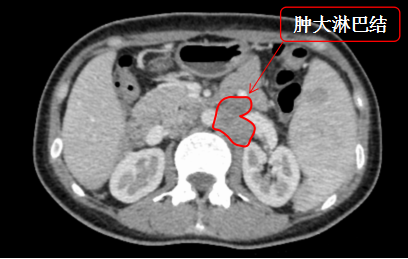

治疗前